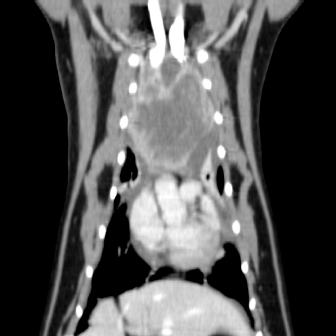

Fig. 1. Computerized tomography of the cranial mediastinal mass (sagittal plane).

On physical examination, the cat had an unkept coat, reduced respiratory sounds cranially, and persistent stridor, but was otherwise bright and ambulatory. Computed tomography (CT) was performed using a Phillips Brilliance six slice CT. Multiphase contrast-enhanced CT images of the head, thorax, and abdomen were acquired with the cat in sternal recumbency (Figs. 1 and 2). A cranial mediastinal mass measuring 60 × 40 mm causing dorsal tracheal displacement toward the right was identified. With contrast administration, there was moderate enhancement of the periphery (+60 Hu) and poor central enhancement (+10 Hu). There was moderate to marked compression of the cranial vena cava, with a focal intraluminal contrast-filling defect at the cranial aspect of the vena cava just caudal to the mass. Here, the path of the cranial vena cava could not be completely traced, suggesting almost complete compression or invasion. There was no evidence of subcutaneous edema of the head or cervical region. Moderate volume of pleural fluid was bilaterally present. Multifocal, slightly branching soft tissue conglomerates largely following the bronchi of the caudal lobes toward the apex was noted, most likely to be bronchial disease with bronchiolar consolidation. Pulmonary metastatic neoplasia was considered to be unlikely. Surgical resection in the form of debulking was recommended on the basis that the large cranial mediastinal mass was most likely the cause of the cat’s clinical signs, and that reduction of gross disease should improve survival time as well as being more responsive to adjunctive treatment with chemotherapy. The cat was then started on mirtazapine (1.875 mg orally every 48 hours) and prednisolone (5 mg orally every 24 hours).